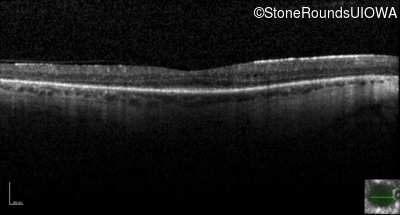

Optical Coherence Tomography - Left - 20/40 -1

Exemplar / OCT Stack

OCT Stack